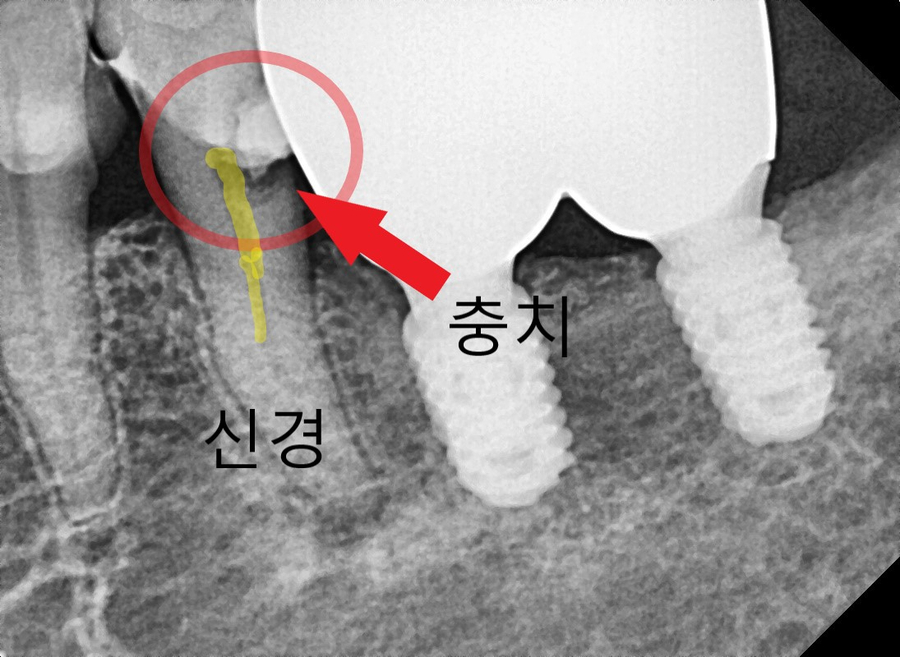

250321

1년 반이라는 시간이 꽤 길었던 건지

이미 충치가 많이 커진 상태였어요.

환자분도 말씀하시기를

아프지 않아서 괜찮은 줄 알고 정기검진일에 안 왔다고 하시더라고요.

1년 반 전 엑스레이 사진과 그 후 사진입니다.

충치 크기 차이가 꽤 많이 나죠?

이미 신경까지 침범한 충치로 인해

신경치료를 결정할 수밖에 없었습니다.